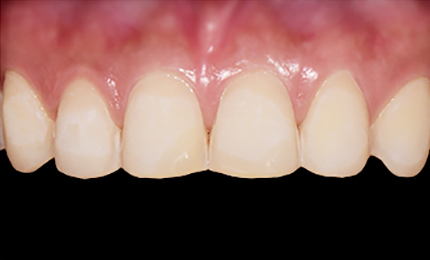

서울바른훈치과 라미네이트 전후 사례

• 시술전

무삭제 or 최대 0.1mm 폴리싱

시술 후